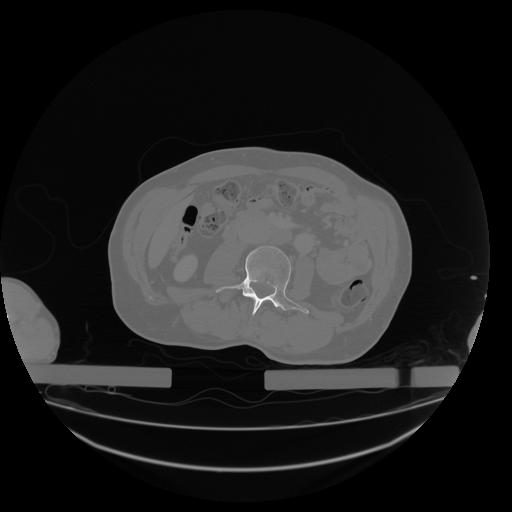

34 CUERPO,CE,Vol,1.0,CUERPO,,